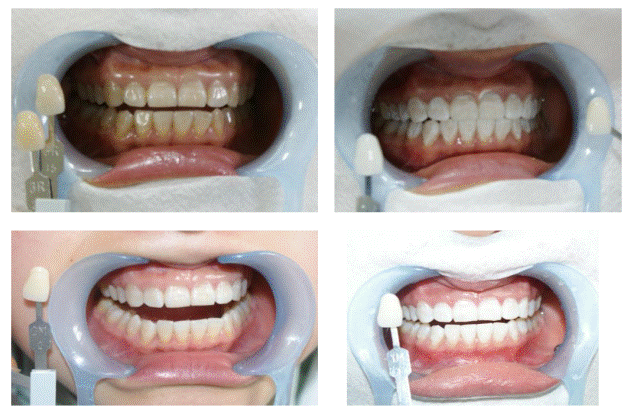

A3冷光美白技术是采用高强度蓝光,隔除有害的紫外线与红外线,将美白剂快速渗透至牙齿深层,与深层的色素发生置换反应,从而达到美白牙齿的效果。整个冷光照射仅需30分钟,美白剂不接触牙龈,对牙齿结构及牙釉质不会造成伤害。

冷光美白术对于着色牙、轻中度四环素牙、氟斑牙等具有很好的美白效果。

图:重度四环素牙的冷光美白(连续两次治疗效果)